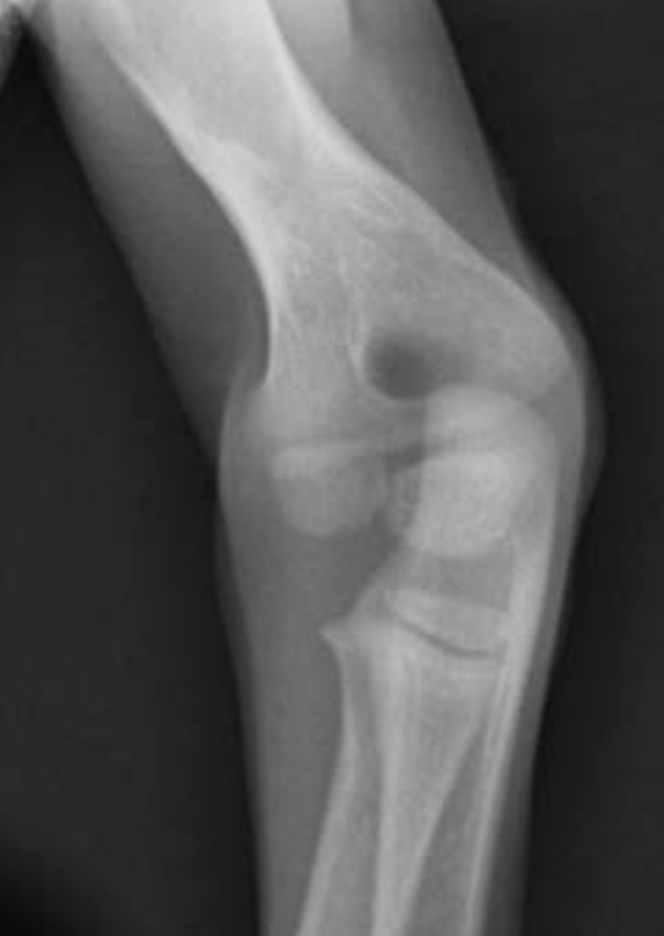

3.5m Yorkie

lateral humeral condylar fracture - see its caudal displacement, superimposed over the cranial ulna.